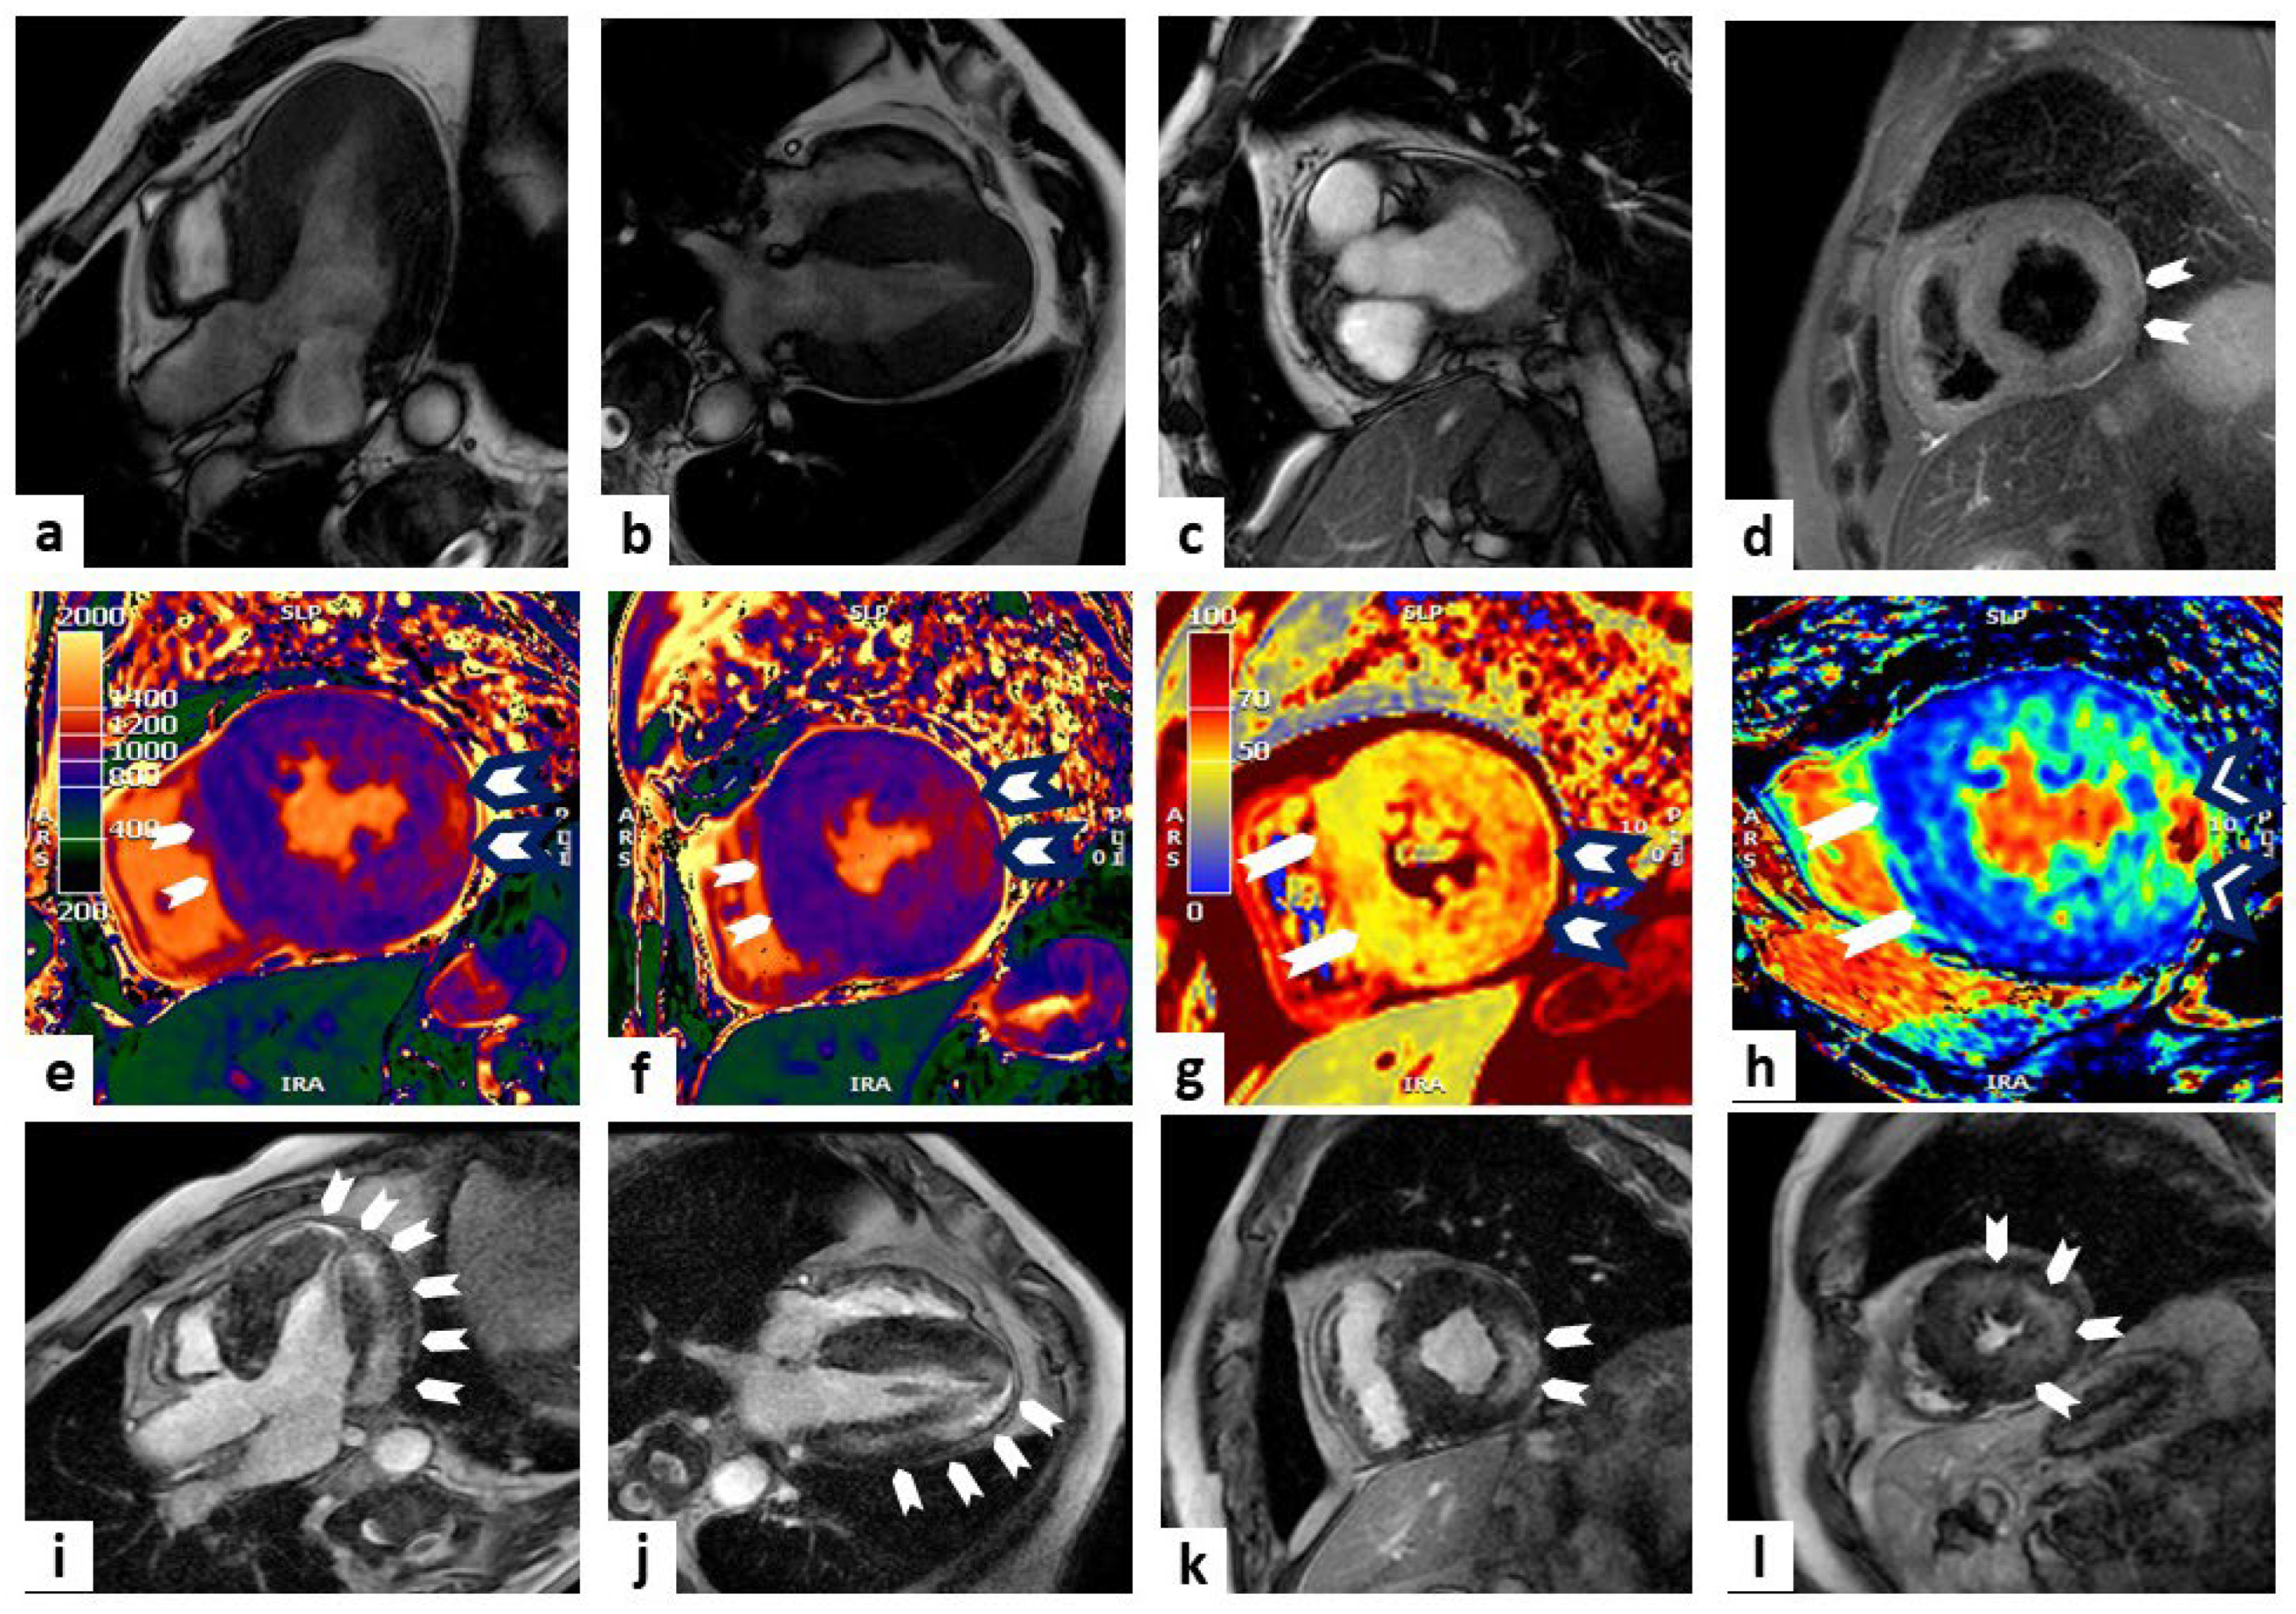

The presence and extension of fibro-fatty myocardial replacement (ARVC pathologic hallmark) can be detected using LGE imaging and is found in up to 88% of patients, with a diagnostic accuracy of 98% when wall motion alterations and pre-/post-contrast signal abnormalities were considered together [78,79,80], although LGE can be detected in other conditions (e.g., sarcoidosis, rheumatic disease, myocarditis), and its interpretation can be difficult due to RV limited thickness [81] (Figure 4).

Figure 4.

Arrhythmogenic right ventricular cardiomyopathy. A case of a 50-year-old female with a history of premature ventricular beats. Cardiac magnetic resonance (CMR) imaging showed multiple bulging of both LV and RV ventricles (white arrowheads) in steady-state free precession (SSFP) sequences (panels (a,b) show 2 slightly different four-chamber views). Possible fat infiltration of posterolateral wall emerged by proton density (PD) sequences (white arrows in panel (c) displaying a mid-LV short-axis view). Panels (d–f) show short-axis views of the mid-LV at T1 and T2 mapping and ECV, respectively, with evidence of a higher value at the level of the lateral wall compared to the remaining myocardium (white arrows). Late gadolinium enhancement (LGE) sequences displayed a non-ischemic hyper-enhancement pattern (white arrows) at the level of the septum, LV, and RV multiple positions (panels (g–i) show four-chamber, three-chamber, and mid-LV short-axis views, respectively). These findings are diagnostic for biventricular arrhythmogenic cardiomyopathy.

More controversial is the role of CMR mapping as a tool for ARVC diagnosis and risk stratification. CMR mapping, recognizing areas of fibrofatty replacement in the RV, can be useful for discovering early stage disease and guide patient management [82]. In the study by Bourfiss et al., patients with genotype-positive ARVC and their at-risk family members have higher native T1 values compared to controls [83].

CMR represents the best imaging technique to quantify myocardial IO. Due to its paramagnetic effect, iron modifies MRI signal intensity, decreasing T1, T2, and T2* relaxation times [103,104]. T2*-mapping, using gradient echo sequences, is particularly useful to identify magnetic field alterations and is currently the gold standard in IOC diagnosis [105]. A three-tier risk model for cardiac IO should be used: low risk if T2* values > 20 ms; intermediate risk if T2* values are from 10 to 20 ms, suggesting mild to moderate myocardial iron deposition; and high risk if T2* values < 10 ms, suggesting severe iron deposition [21]. Since reduced cardiac T2* is associated with an increased risk of heart failure, ventricular arrhythmias, and death, T2* monitoring has a crucial role to guide chelation therapy and assess iron overload status [106,107]. Furthermore T1- and T2-mapping can be helpful to detect patients with only mild cardiac IO, with high sensitivity and specificity [108,109]. LGE and increased ECV can be detected in patients with IO, reflecting diffuse myocardial fibrosis [110,111]. Feature tracking CMR strain imaging is a sensitive parameter for early prediction of systolic dysfunction, even in patients with normal T2* values [112] (Figure 5).

Figure 5.

Iron overload. A case of a 38-year-old man in follow-up for thalassemia. Cardiac magnetic resonance (CMR) imaging showed a mild reduction in left ventricle ejection fraction (LVEF) in steady-state free precession (SSFP) sequences (panels (a–c) show four-chamber, two-chamber, and mid-LV short-axis views, respectively). The T2* sequences showed a normal value of iron in the heart (T2* > 20 msec), with a pathological value of iron in the liver (T2* 9 mg/g); panels (d–f) show the mid-LV short-axis view, the colorimetric display of T2* at the same level, and the graphical curve of T2* decay expressed in msec, respectively. T1 mapping showed a lower value of T1 (mean T1 900 msec), suggesting iron overload in the heart; panels (g–i) show the basal-LV short-axis, mid-LV short-axis, and apical-LV short-axis views, respectively (white stars).